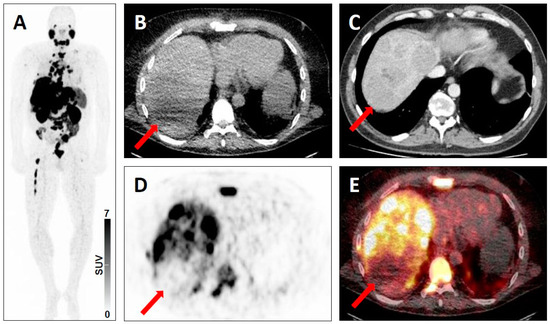

| 4 | - Intense uptake in a liver lesion without definitive findings on conventional imaging [20] | - Intense radiotracer uptake in a lymph node without definitive findings on conventional imaging [19] | |

| 5 | - Intense uptake in a liver lesion with definitive findings on conventional imaging [20] | - Extensive metastatic PC with diffuse osseous metastatic disease and intense radiotracer uptake (“superscan“ on PSMA-PET/CT) [19] | |